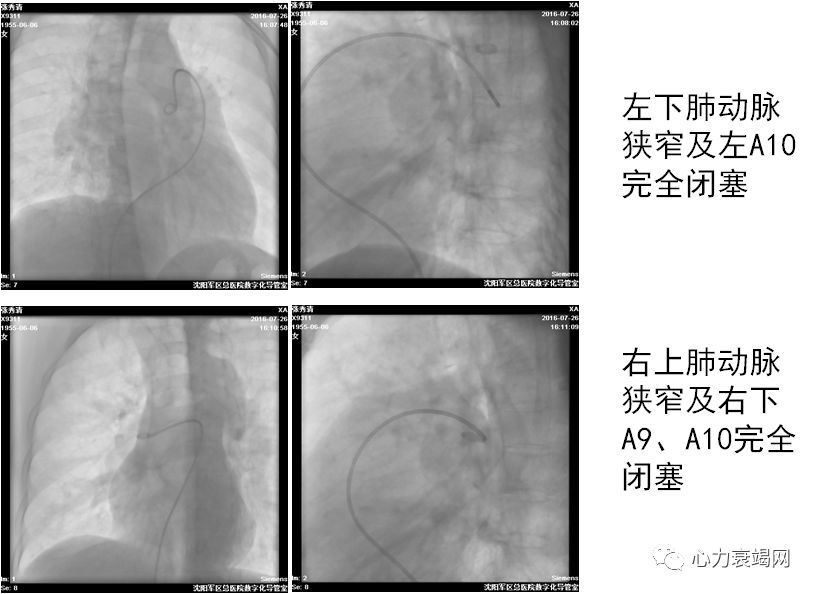

活动后胸闷、气短8年于2016年7月20日入院

确诊CTEPH 8年,拒绝肺动脉内膜剥脱术,服用华法林2年

CTPA阴性

球囊扩张术后肺动脉压力由120/48(72)mmHg降至90/32(51)mmHg